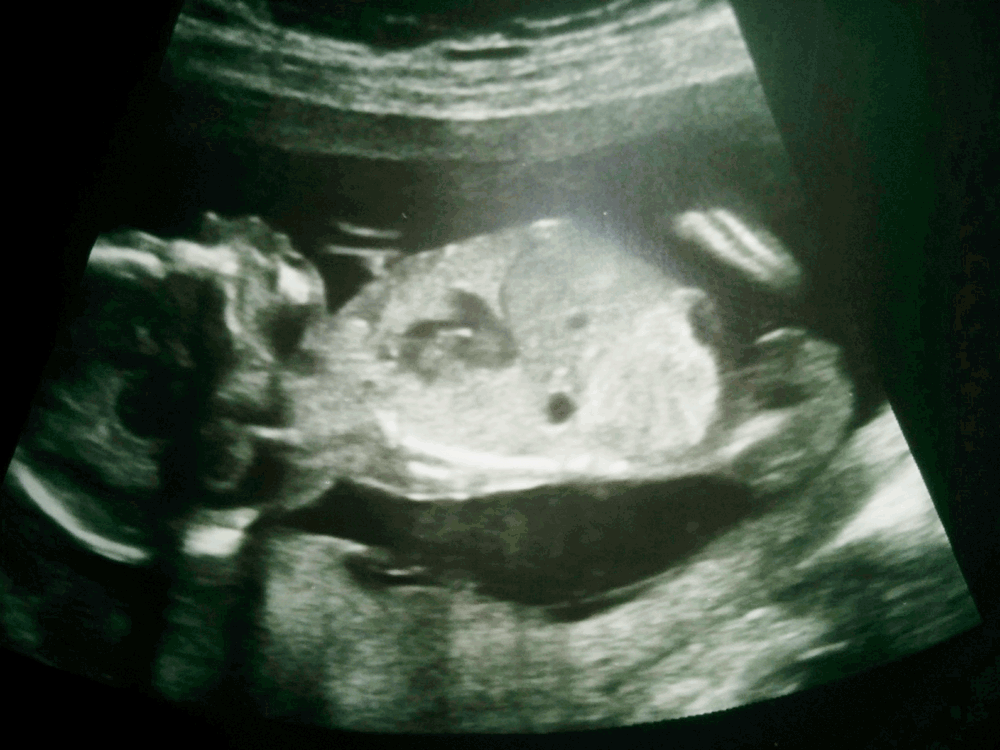

15+5 shot - Guesses?

Hi all, do you have any guesses from this pic?